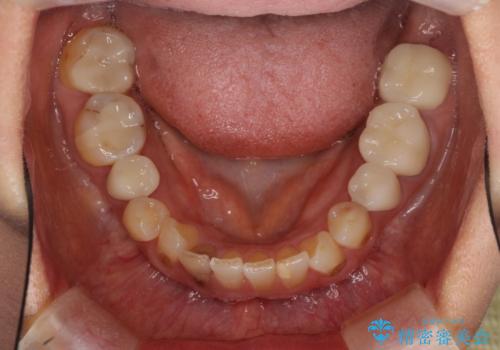

- 目立つ銀歯を気にして来院された患者様です。

奥歯を中心に銀歯が多く装着されており、一部の歯は咬合時に痛みを感じている状態でした。

必要な歯に根管治療を行い、オールセラミッククラウンにて補綴治療を行うこととしました。

一部根管治療では症状が改善しなかったため、歯根端切除術を行いました。